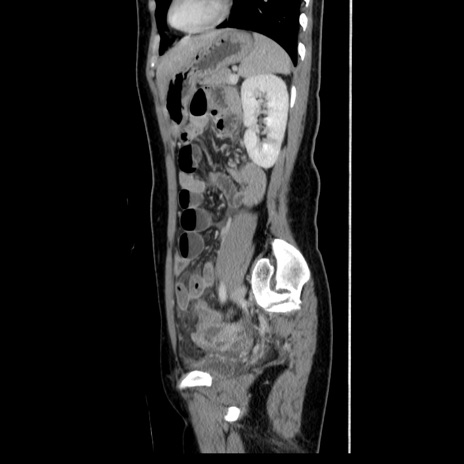

症例39(矢状断像)

【症例】40歳代女性

【主訴】上下腹部痛

【現病歴】2日目から下腹部痛あり。夜間は痛みで眠れなかった。昨日より上腹部痛と下痢が出現。臥位で痛みは軽快したため、休んでいた。本日になって臥位でも立位でも痛みが強くなってきたため救急要請。

【既往歴】子宮内膜症

【身体所見】部:平坦・軟、左上下腹部に圧痛あり、反跳痛あり。

【データ】WBC 21800、CRP 26.78

CT